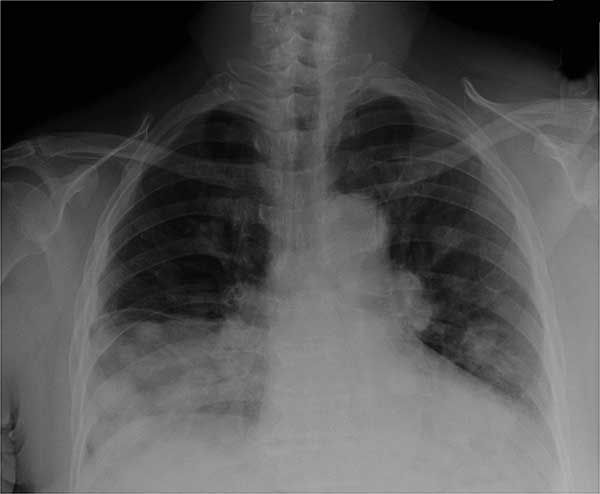

The initial chest radiograph showed multiple pulmonary masses of varying sizes with a large right middle lobe opacity and hilar adenopathy (Figure 1). A CT scan of the chest confirmed a 9.5 × 8.3-cm right middle lobe mass, 3.7 × 2.9-cm and 3.1 × 2.2-cm right lower lobe masses, a 3.6 × 2.0-cm left upper lobe mass, and innumerable diffuse smaller nodules throughout the lung fields (Figure 2).

Figure 1–Multiple pulmonary masses of varying sizes and hilar adenopathy can be seen in this chest radiograph.